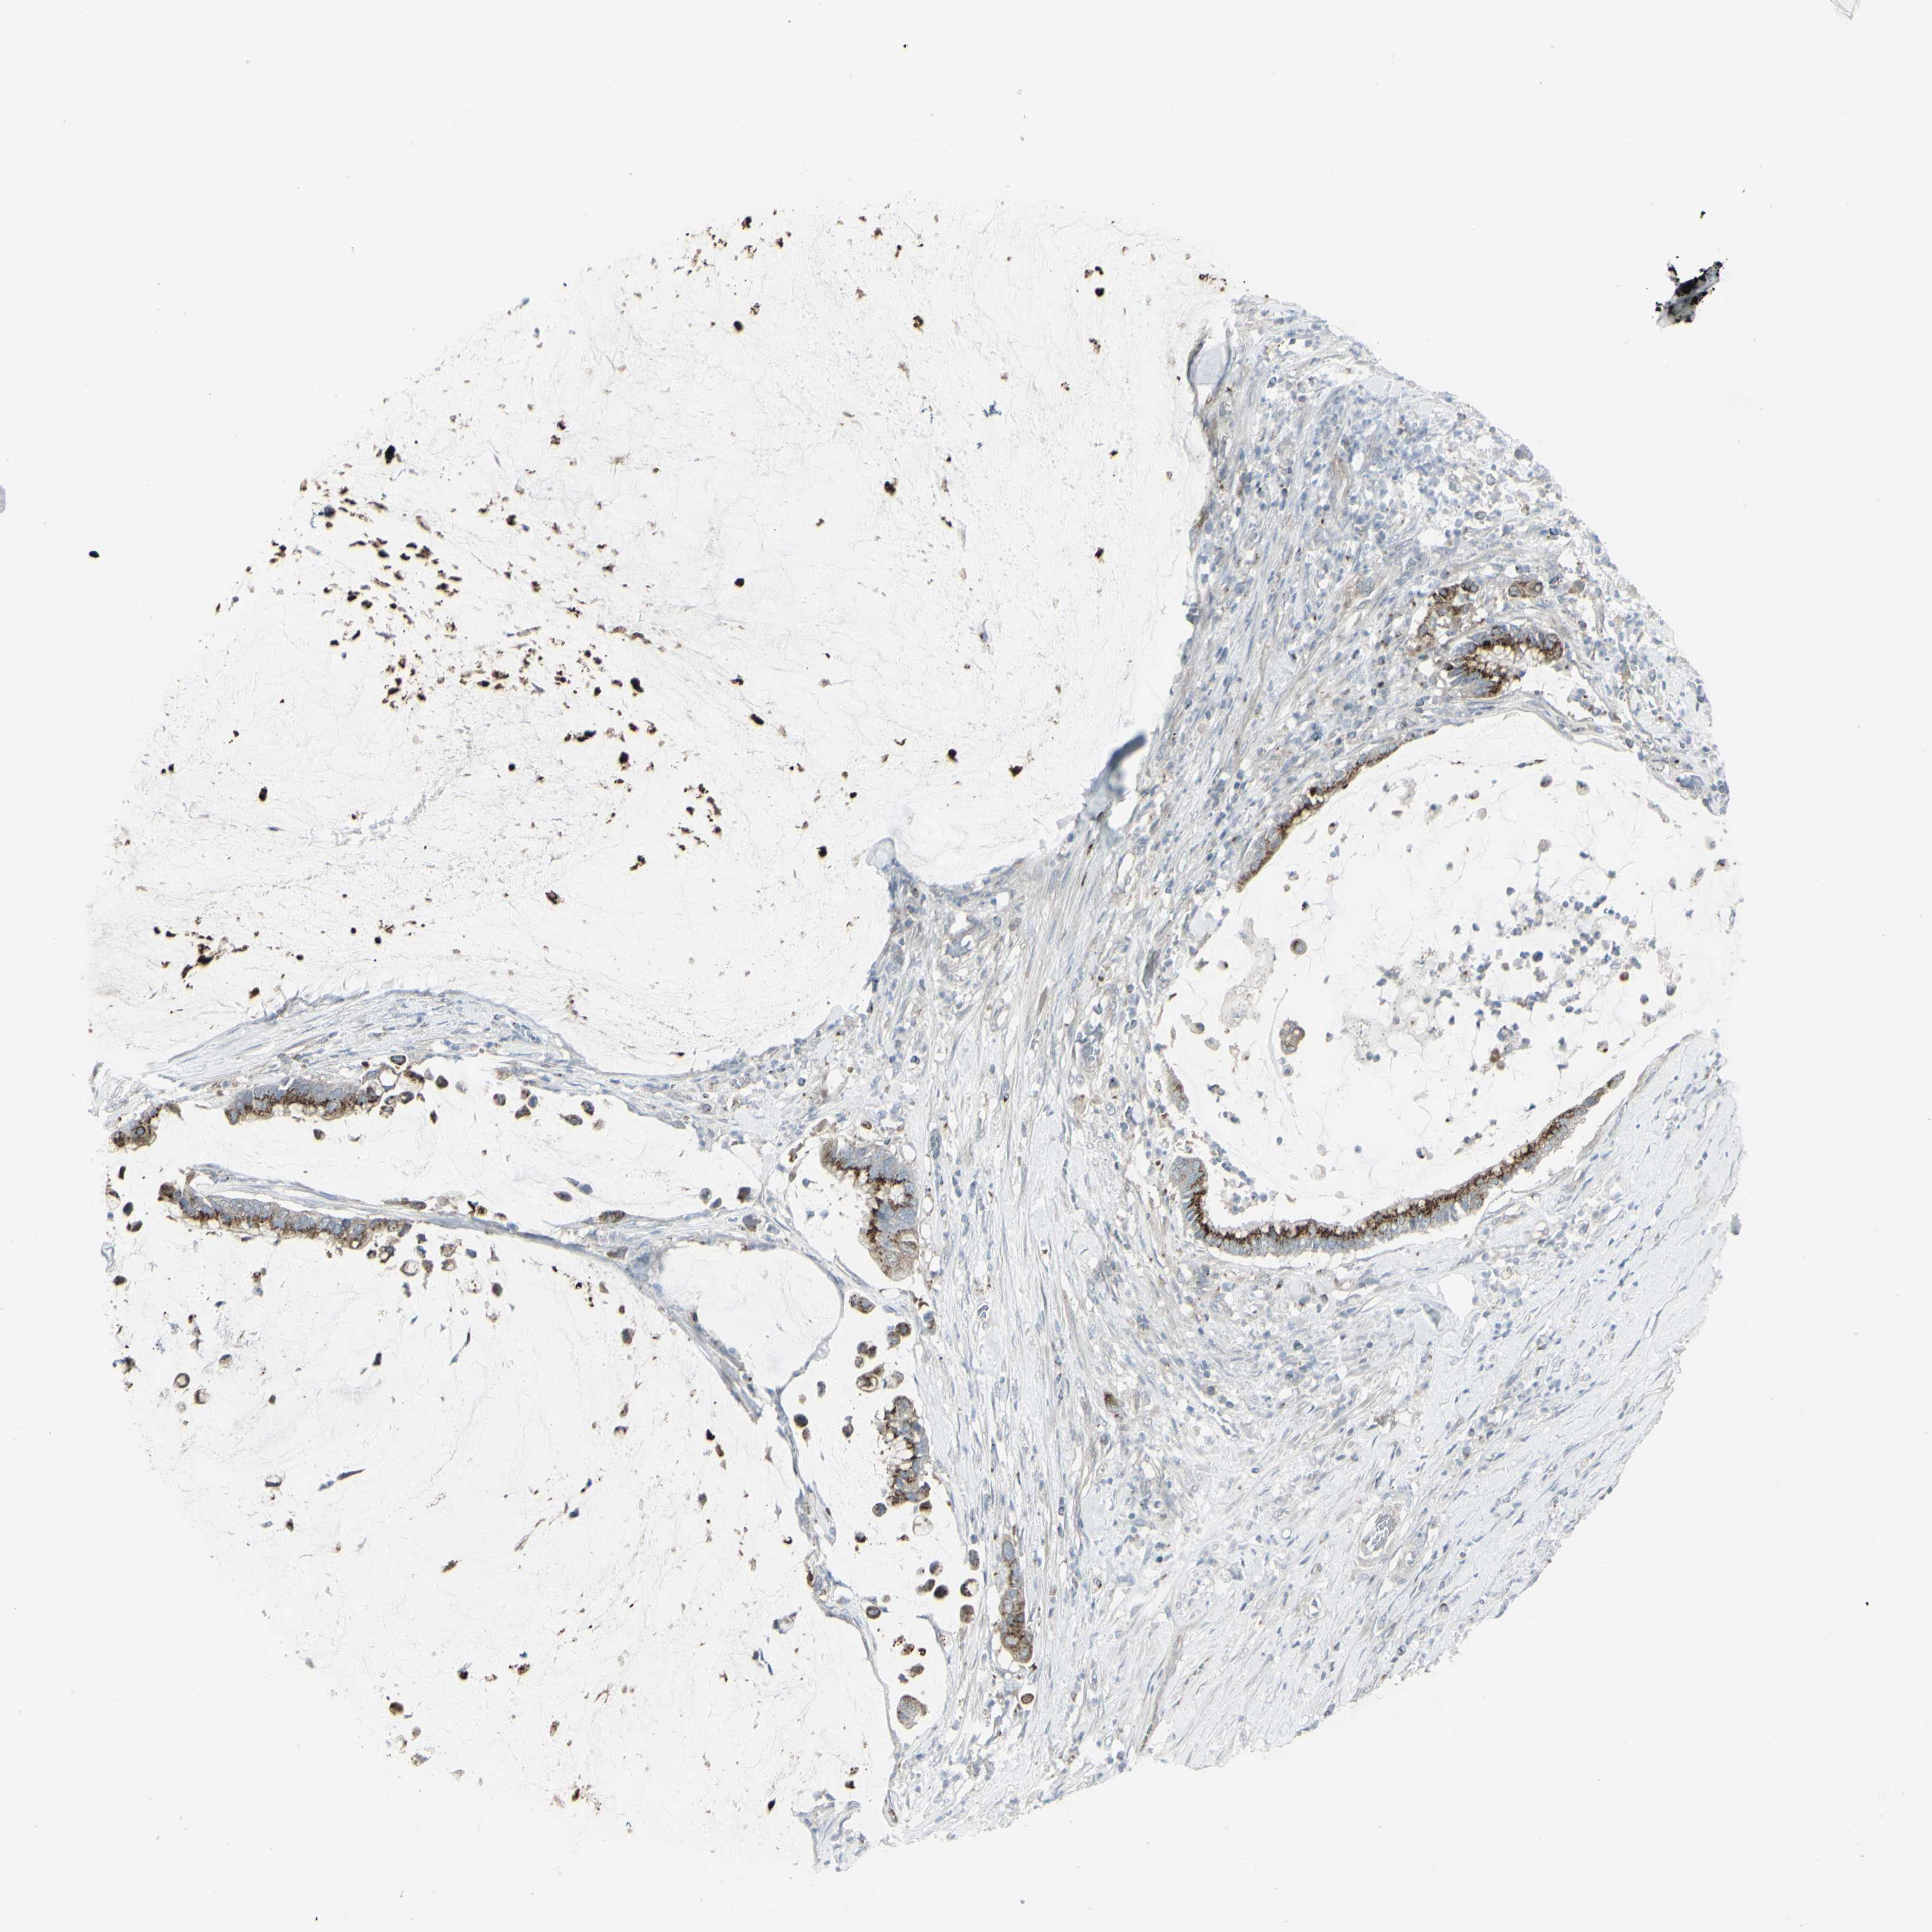

PANCREATIC CANCER - Protein expressioni

A mouse-over function shows sample information and annotation data. Click on an image to view it in a full screen mode. Samples can be filtered based on level of antibody staining by selecting one or several of the following categories: high, medium, low and not detected. The assay and annotation is described here.

Note that samples used for immunohistochemistry by the Human Protein Atlas do not correspond to samples in the TCGA dataset.

Antibody stainingi

Antibody staining in the annotated cell types in the current human tissue is reported as not detected, low, medium, or high, based on conventional immunohistochemistry profiling in selected tissues. This score is based on the combination of the staining intensity and fraction of stained cells.

Each image is clickable and will lead to virtual microscopy that enables deeper exploration of all samples and also displays staining intensity scores, fraction scores and subcellular localization as well as patient and tissue information for each sample.

Antibody HPA011762

Antibody HPA017086

Staining

High

Medium

Low

Not detected

Intensity

Strong

Moderate

Weak

Negative

Quantity

>75%

75%-25%

<25%

None

Location

Nuclear

Cytoplasmic/membranous

Cytoplasmic/membranous,nuclear

Adenocarcinoma, NOS

Adenocarcinoma, metastatic, NOS